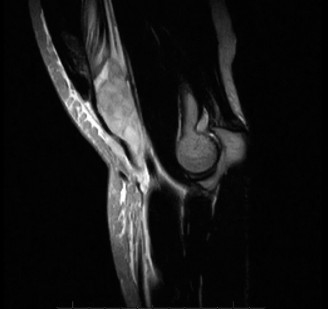

Treat a patient with scapular winging? CASE 23 A 47-year-old, right-hand-dominant male presents to your clinic complaining of right shoulder weakness for the past 2 months. He denies any history of trauma but notes sudden onset of pain 2 months ago that lasted approximately 2 weeks and then subsided without any intervention and was followed by shoulder weakness. He works as a lawyer and has been going through a divorce for the past year. Physical examination reveals no tenderness to palpation about the shoulder. He has decreased sensation over the lateral aspect of the shoulder, decreased muscle bulk over the left shoulder compared with the contralateral side, and weakness with left shoulder abduction. He is distally neurovascularly intact. The patient had already been referred for an x-ray and MRI by his primary care doctor that are shown in Figures 2–62 and 2–63.

Figure 2–62

Figure 2–63

The correct answer is (C). The patient’s decreased sensation over the deltoid, deltoid muscle atrophy on examination, and MRI with atrophy of the teres minor points to axillary nerve dysfunction. Suprascapular nerve injury (Choice A) would result in atrophy of the infraspinatus and or infraspinatus muscles, leading to weakness with external rotation and/or forward flexion. Dorsal scapular nerve injury (Choice B) would result in weakness of the rhomboid muscles and levator scapulae. While injury to the posterior cord of the brachial plexus (Choice D) would result in symptoms of axillary nerve palsy, they would also involve dysfunction of the radial nerve, which also comes off the posterior cord.